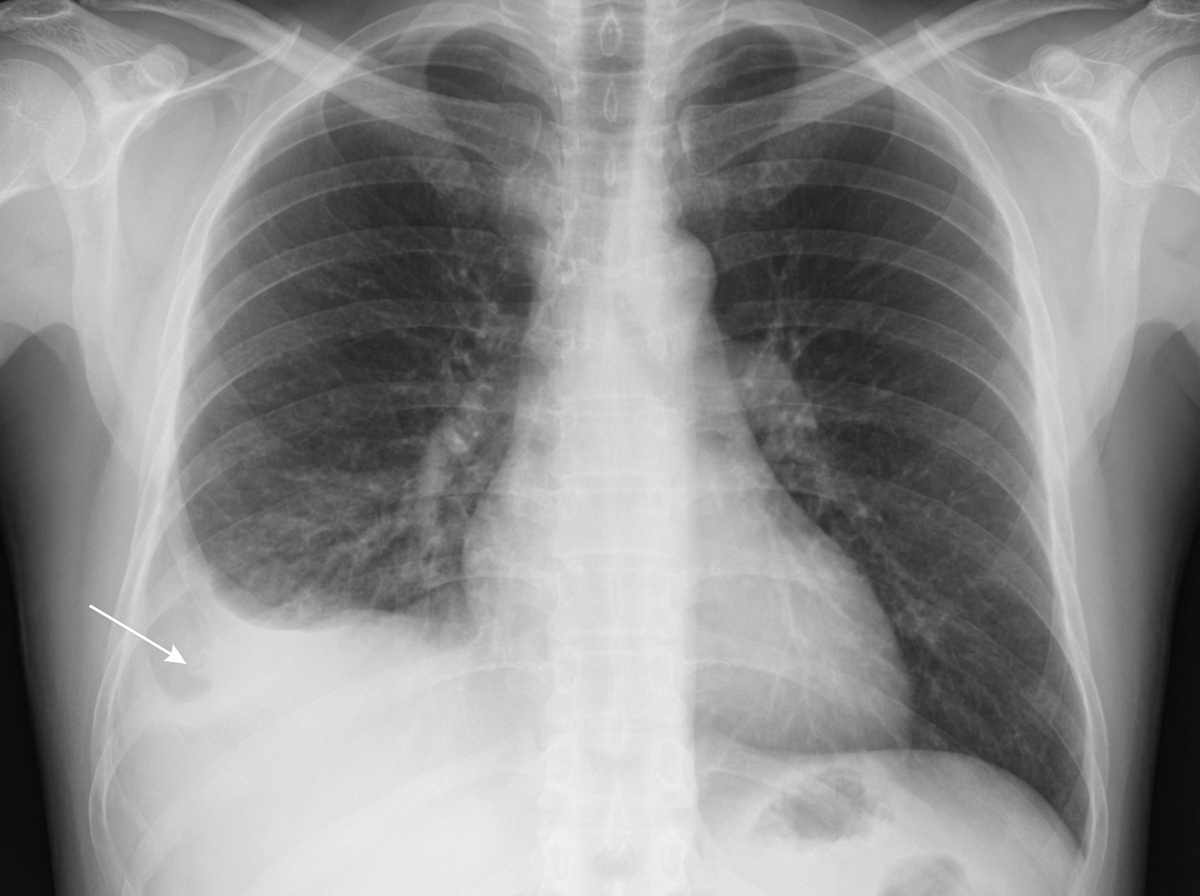

A patient with a known history of pulmonary tuberculosis presents to the emergency room with dyspnea. A chest X-ray reveals specific findings. Which of the following structures is NOT pierced during a diagnostic tap performed from the indicated structure?

Explanation: ***Visceral pleura*** - During **thoracocentesis**, the needle stops in the **pleural space** between the parietal and visceral pleura to aspirate fluid, never penetrating the visceral pleura. - The visceral pleura is closely adhered to the **lung surface** and piercing it would cause **pneumothorax** and lung injury. *Serratus anterior* - This muscle is pierced during thoracocentesis as the needle passes through the **chest wall** in the **mid-axillary line**. - It lies superficially in the **lateral chest wall** and is routinely traversed during the procedure. *External intercostal muscle* - The needle must pierce the **external intercostal muscle** as part of the intercostal space anatomy during thoracocentesis. - It runs **obliquely downward and forward** between adjacent ribs and is always encountered during pleural tap. *Endothoracic fascia* - This **deep fascial layer** lines the inner surface of the chest wall and is pierced before reaching the **parietal pleura**. - It separates the **intercostal muscles** from the parietal pleura and must be traversed during thoracocentesis.